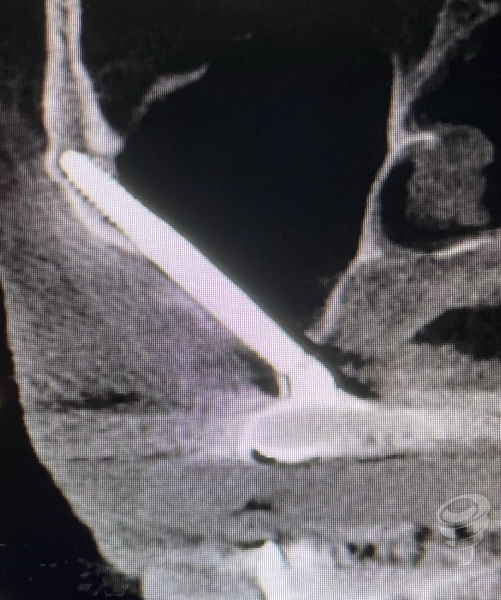

Esto ha sido posible por la evidencia de que la estabilidad del implante cigomático no depende de un anclaje en 4 corticales sino del anclaje en el cuerpo del malar. Esta «no necesidad» de anclaje cortical nos permite también mantener el implante en el espesor del malar, sin necesidad de perforar su cortical externa y reduciendo así el riesgo de fístulas cutáneas futuras.

En la imagen 4 podemos observar un implante confinado en el espesor del malar, sin necesidad de perforar su cortical externa, reduciendo así el riesgo de fístulas cutáneas.

Imagen 4